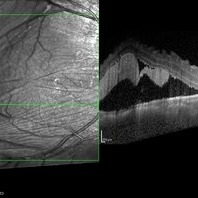

Multifocal Exudative Detachments Due to VKH

May 14 2014 by Avris Romario Diparaja Siahaan

OCT a 38-year-old man with multifocal CSR and inferior exudative retinal detachment on both eyes (Harada Syndrome).

Photographer: Avris Romario Diparaja Siahaan, Klinik Mata Nusantara

Imaging device: Heidelberg HRA + OCT Spectralis

Condition/keywords: multifocal central serous chorioretinopathy (CSCR), optical coherence tomography (OCT)